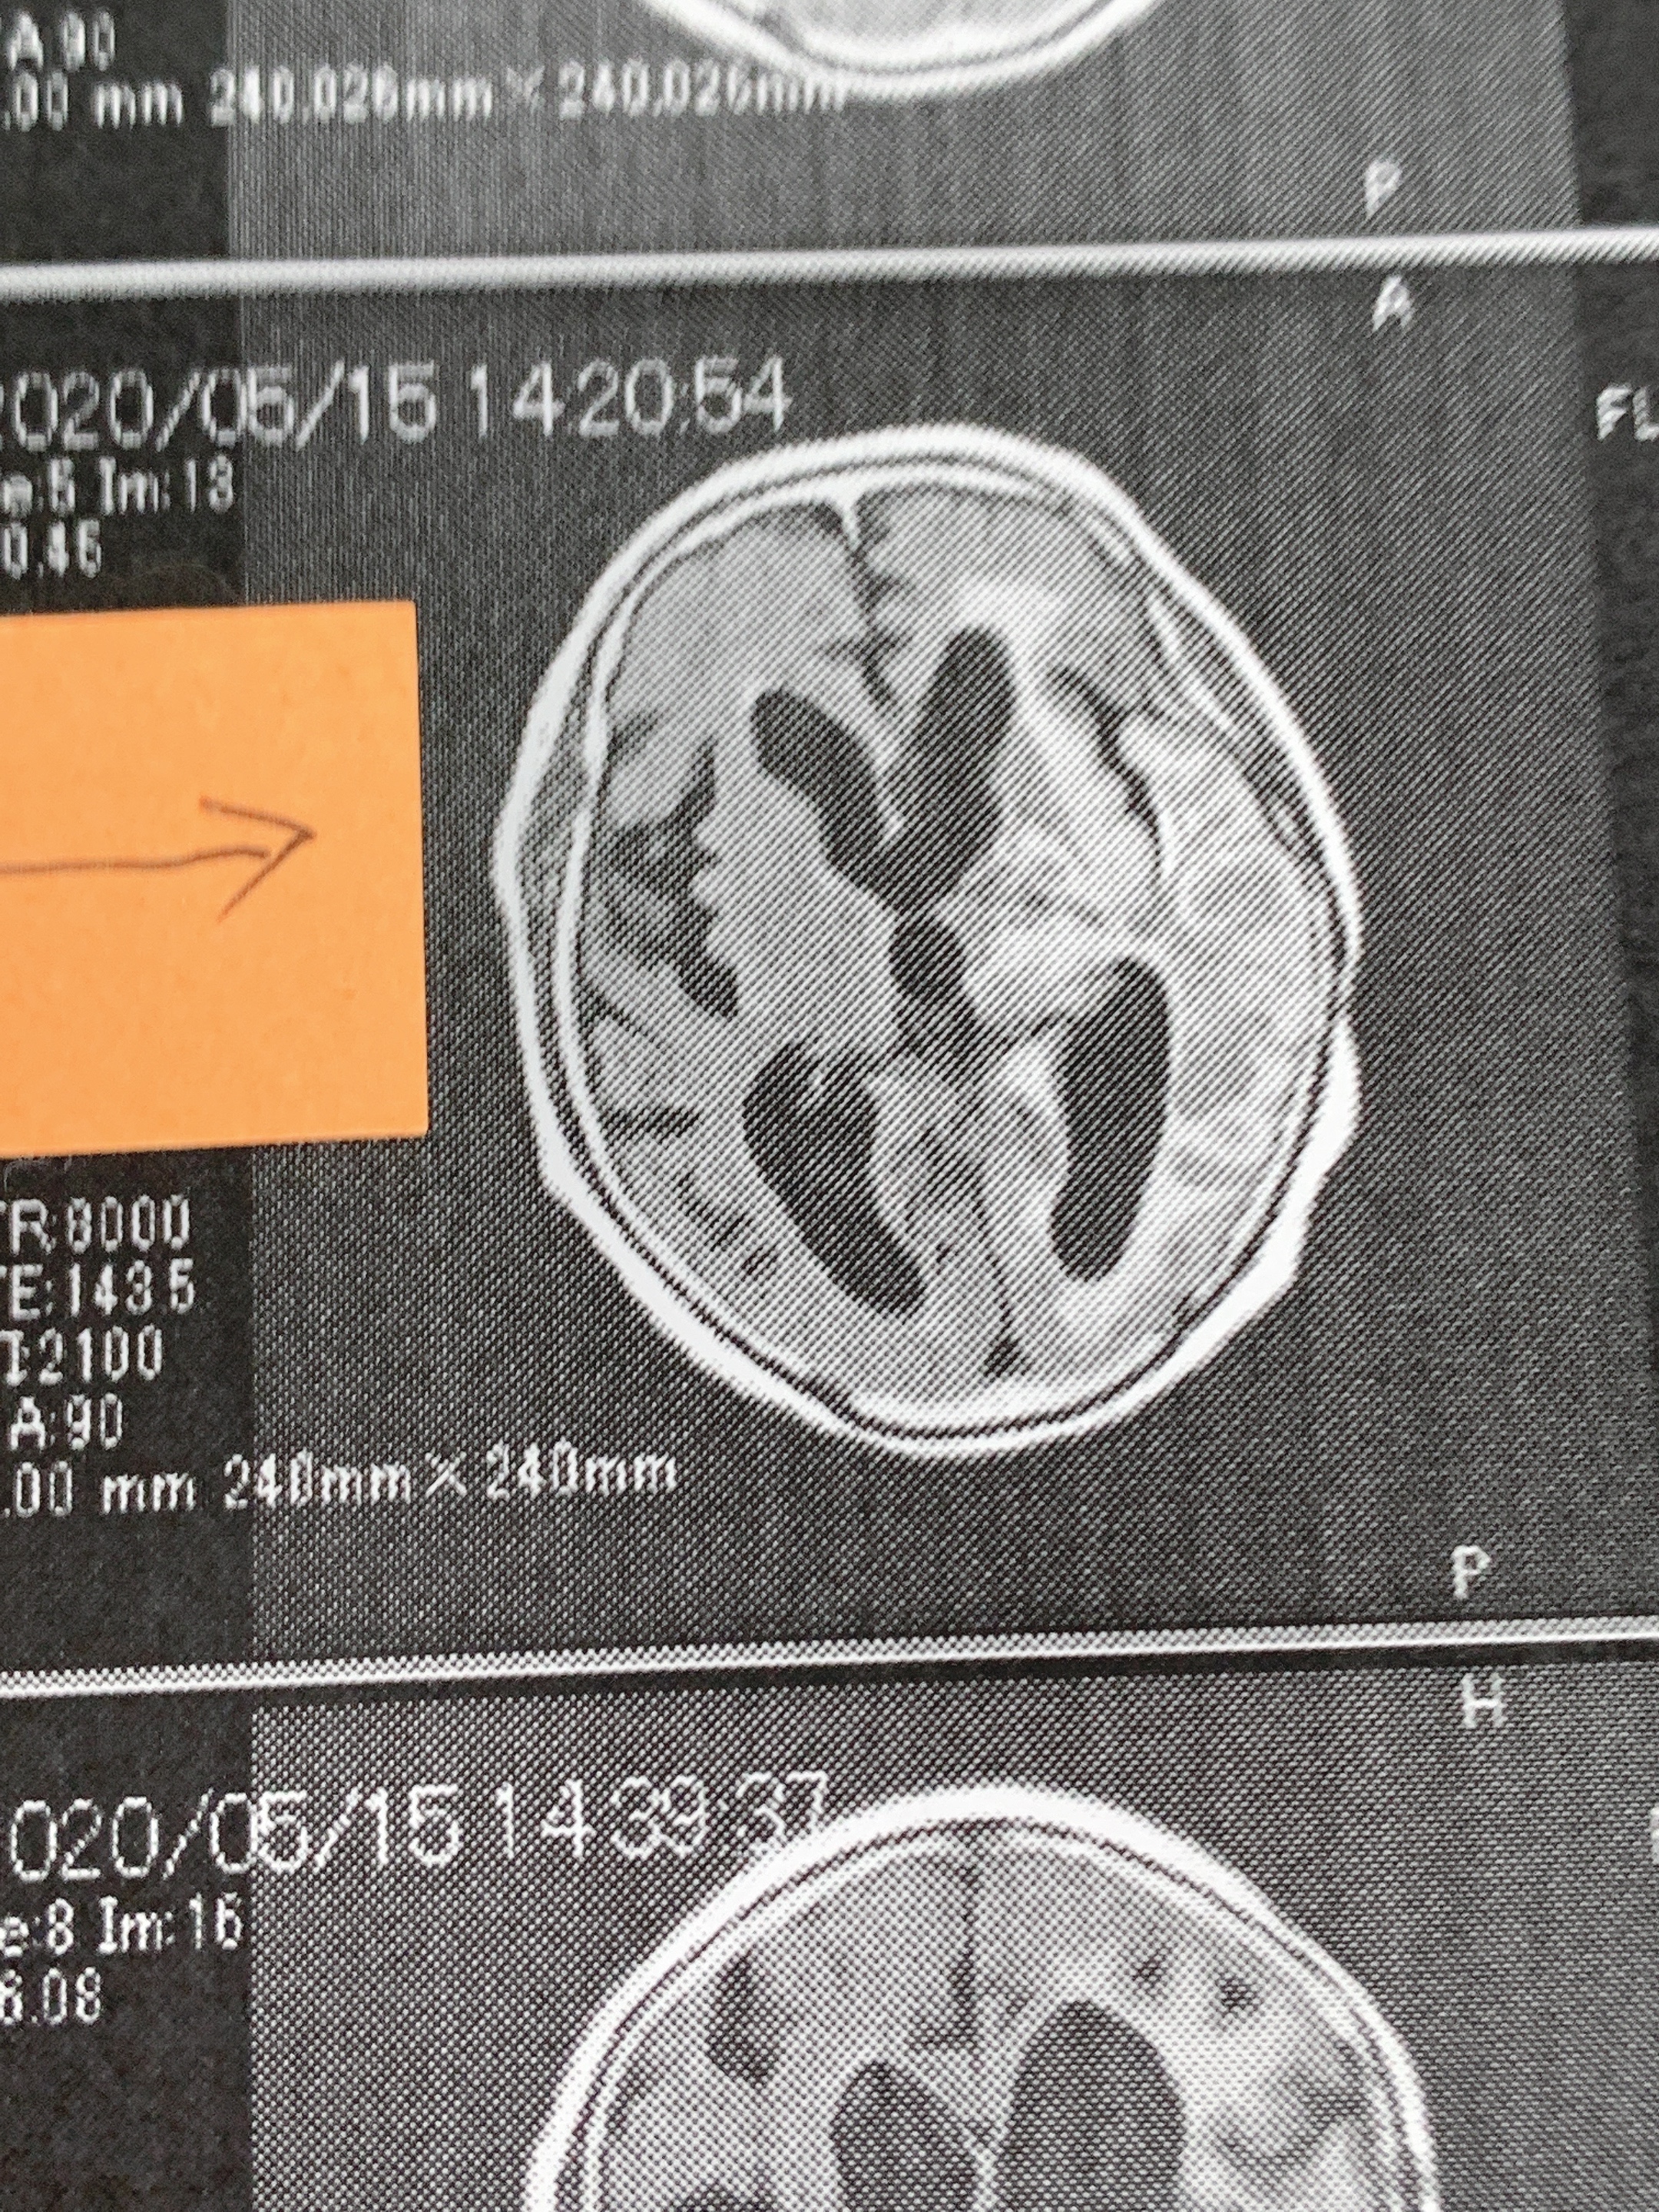

脳腫瘍の浮腫が2カ月で改善された画像です!!

先日、書いてます患者さんの画像をご覧ください。